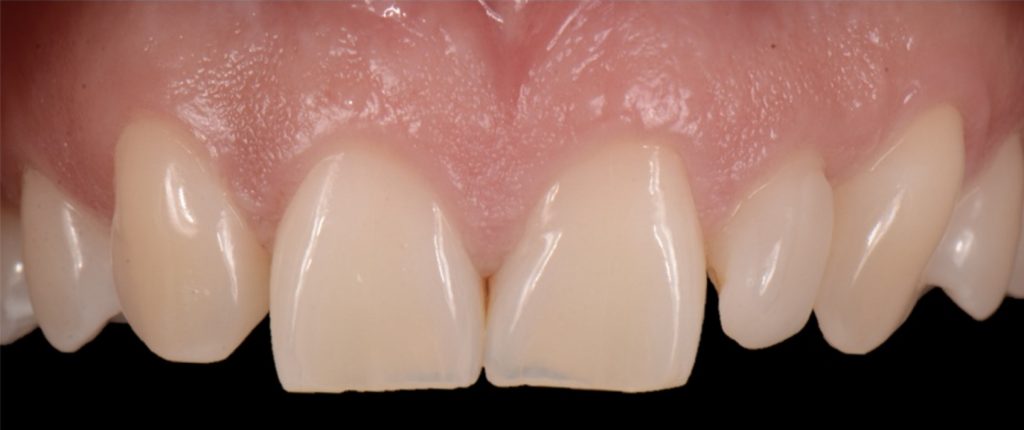

Solution #1: Canine Substitution for Missing Lateral Incisors

Canine substitution is the least invasive option and a popular alternative, but it often poses esthetic and functional challenges that need to be considered and cleared (Fig. 1). From an esthetic standpoint, the canine’s shape and shade must be considered. From a contour standpoint, the width of the canine should be evaluated because they are generally larger than lateral incisors.

However, the most critical aspect to manage is the CEJ width because it cannot be narrowed. The wider the tooth at the CEJ, the more difficult it is to make a canine look like a lateral incisor. Moreover, canines typically present with a very distinctive root eminence, and if it is particularly accentuated, it could become yet another esthetic challenge — one commensurate with the patient’s lip mobility.

There is no major esthetic concern for patients where a low lip line conceals the gingival outline. Still, if there is high lip mobility and the gingival outline is not concealed, such an eminence could represent an unacceptable esthetic problem.

From a shade standpoint, canines usually are the teeth with the most saturated chroma in the maxillary arch, which often creates an esthetic challenge where this oversaturation is evident.

Consequently, considering these aspects, the ideal clinical scenario for canine substitution would be in patients with smaller shaped canines that are not oversaturated with chroma and in patients who display low lip mobility.